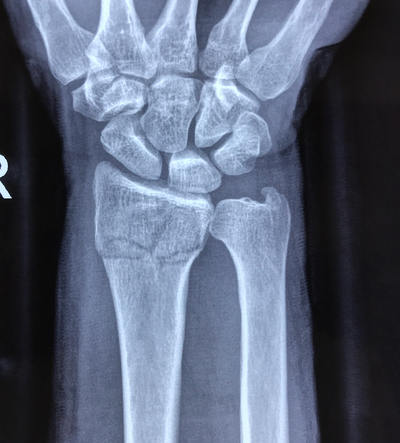

3种手术治疗方式应对桡骨远端骨折!

桡骨远端骨折属于常见的上肢骨折疾病,随着社会发展,工作及生活节奏不断加快,车祸和高处坠落等也会使得桡骨远端严重骨折的发生率明显上升。

桡骨远端骨折分型为Frykman分型AO/ASIF分型,其中AO/ASIF分型更加详细,可信度明显更高。

桡骨远端骨折属于上肢较为常见的骨折疾病,在实施评估的时候,通常进行计算机断层扫描(CT)分类,且在所有分类系统中应用x射线的时候,观察者之间的一致性程度显示为中等到中等。